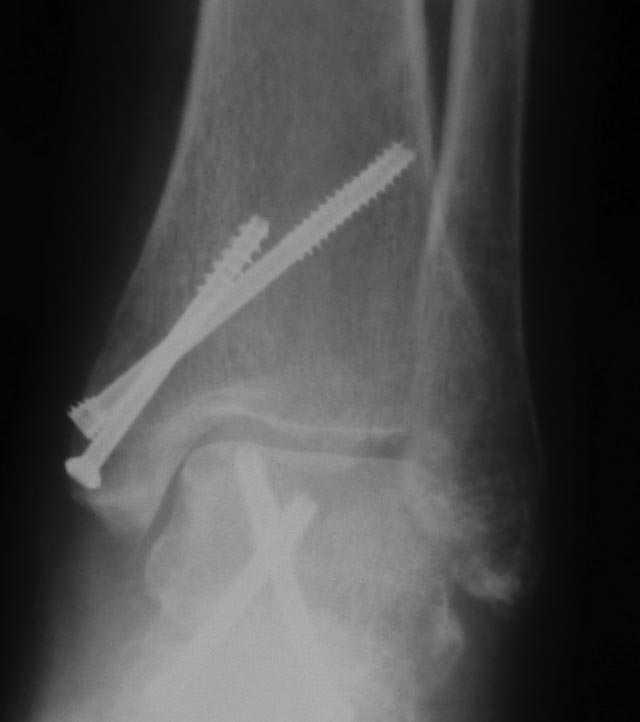

Re: Артроскопический остеосинтез таранной кости

Два дня был без доступа к интернету. Во вложении недавний случай остеосинтеза оскольчатого переломовывиха таранной кости. Методика классическая. С анатомической репозицией и стабильной фиксацией. Без гипса после операции.